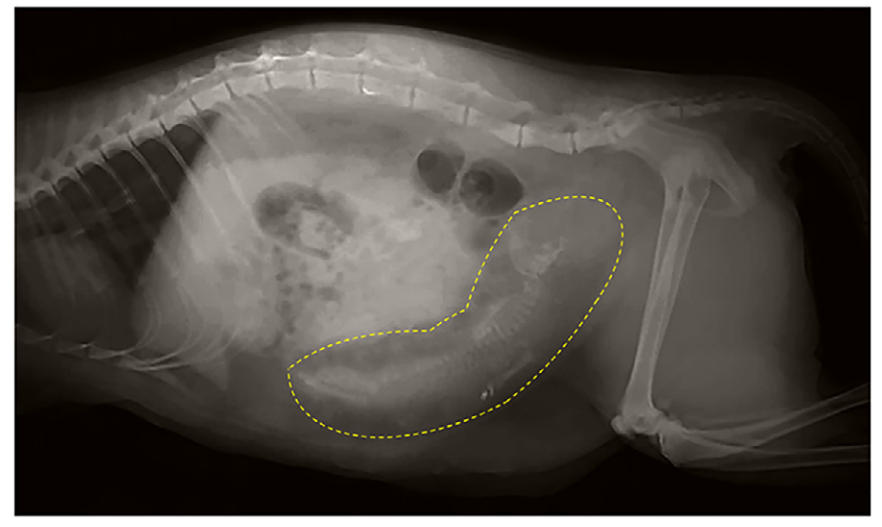

在进行深度触诊时,发现后腹腔内有坚实的管状结节结构,延伸至骨盆入口处,同时伴有相应的疼痛反应。腹部X光发现了胎儿骨骼结构(下图),这一发现进一步得到了超声的支持。

↑ 侧腹部X光片显示母猫子宫内有不透射线的胎儿骨骼结构(黄色虚线区域)。